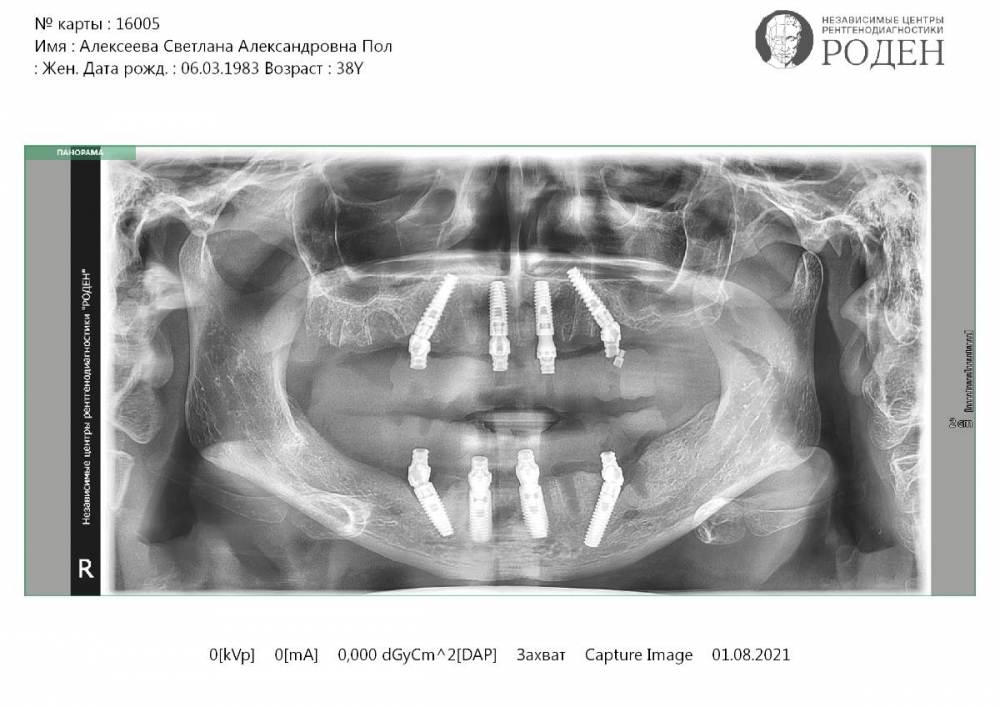

stoliza Опубликовано 2 августа, 2021 Поделиться Опубликовано 2 августа, 2021 Добрый день уважаемые специалисты! Очень прошу Вас помочь с консультацией. По собственной глупости и жадности вляпалась в неприятную историю с полной имплантацией на обе челюсти. Операция была 10 июня. По плану наверху должно быть 6 имплантов, внизу 4. Временный протез предусмотрен не был, обещали сразу ставить постоянный (в плане лечения временный протез тоже отсутствует). Слепки сняли только 4 день, сняли плохо. на 5ый день вызвали переделывать. После операции, дома, я обнаружила, что наверху не 6 заглушек торчит, а всего 4. Я позвонила в клинику, мне ответили, что все нормально, 2 импланта не выведены и находятся в состоянии покоя. На 7 день мне установили протез. протез оказался неудобным, прикус поднят очень высоко, очень большие пустоты между деснами и зубами. Я сообщила об этом доктору, мне сказали терпеть, что через 6 месяцев сделают другой протез, все так и должно быть. Лучше мне не становилось, полторы недели назад у меня началась острая боль снизу слева где-то в глубине десны, болело не постоянно, а только если сомкнуть зубы. Я обратилась в клинику, мне сказали терпеть и приходить через 2 дня, когда будет зубной техник. Я пришла через 2 дня, мне сняли нижний протез. Доктор осмотрела внешние ткани, сказала, что все нормально, вероятно болит костная пластика, снимок делать не нужно, так как с момента установки имплантов прошло очень мало времени и мы ни чего не увидим. 31 числа боль стала постоянной, я не выдержала и пошла делать панорамный снимок самостоятельно. Я не ожидала увидеть там что-то, поскольку не разбираюсь в снимках. Но когда получила результаты исследования оказалось, что наверху стоит не 6 имплантов, наличие которых стоит по плану и по словам врача они просто не выведены, а всего 4, и с одним из них визуально что-то не так. Сегодня, я с этим снимком пойду выяснять, где еще 2 импланта и почему болит снизу слева. но я боюсь, что меня опять обманут, скажут что все хорошо, а по факту просто не сообщат о проблеме (как и о том, что не установили 2 имплантата, что протеза будет 2 и т.д.). Речь уже не просто о деньгах, а о моем здоровье. Я боюсь! Пожалуйста, прокомментируйте снимок. Очень прошу, посмотрите, что с имплантами, может быть Вы по снимку сможете понять, что болит слева снизу. Правильно ли импланты установлены? Что бы придя к врачу я хотя бы понимала, на что нужно обратить внимание, в каком направлении действовать и что вообще происходит. Ссылка на комментарий

Irouil Опубликовано 2 августа, 2021 Поделиться Опубликовано 2 августа, 2021 На представленном снимке действительно по 4 импланта установлено на верхней и нижней челюстях. Явных признаков нарушения протокола все-на-4 я не вижу В качестве дополнительной меры исследования области, которая Вас беспокоит, я могу посоветовать КТ челюстей Ссылка на комментарий

red_butler Опубликовано 2 августа, 2021 Поделиться Опубликовано 2 августа, 2021 по снимку с имплантами проблем не увидел, в одном импланте раскрутился фиксирующий винт, с квитанцией доктор наверное ошибся Ссылка на комментарий